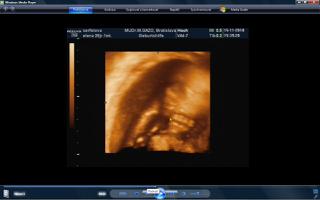

vcera som mala poradnu a teda dopadla pre mna dost prekvapujucu. mala je uz mesiac otocena dolu hlavickou a tlaci sa a tlaci. krcok sa mi zacal skracovat, ale zatial sa neotvara. a aby toho nebolo malo, tak mam aj iritabilnu maternicu. buducu nedelu idem do nemocnice na premeranie krcka a uvidi sa, co bude. aspon, ze ju uvidime 3D potvorku malu nedockavu 🙂 do mesiaca mi zrejme bude treba zaviest pesar.. tooolko radosti naraz a to som povodne vobec nemala mat poradnu, kedze som povodne dosla len s babkou na kontrolu..tak vysetrila aj mna.

caute baby. uz som tu dlho nebola. nejako nestiham. My sme uz boli na tiez na 3D a zase mala mala rucicky pred tvarickou ale daco bolo aj vidno. takze sme zistili, ze sa podoba na muza, teda aspon ten nos usta. Ma skoro 500 g takze je asi o tyzden posunuta neskor.Ak sa mi bude dat tak pridam dake fotky z toho dvd co som vybrala. Inac ja som kupovala tehotenske pancuchy v Brendone v Ba za 4 Eura. teda tenke ale mali tam aj hrubsie a tie stali 15 eur. Ja tiez rozmyslam rodit v ruzinove ale asi skor na Kramaroch. to mam blizsie domov. Ja si doplacam od marca dobrovolne nemocenske poistenie k povinnemu do maximalneho vymeriavaceho zakladu, aby som mala maximalnu matersku. Takze snad s tou materskou sa to bude dat ale horsie to bude s tym rodicovskym prispevkom.